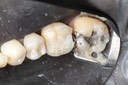

Matt Dodson #3 pre-op